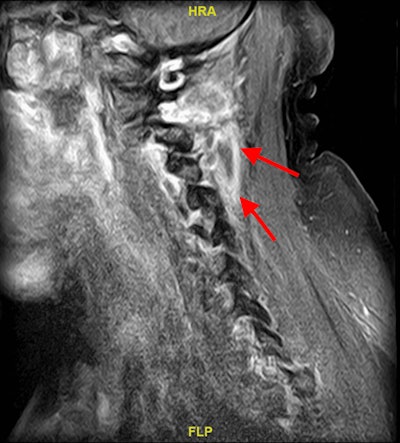

A CT scan of the maxillofacial area with contrast revealed endodontic and periodontal disease involving the molars, and magnetic resonance imaging (MRI) of the lumbar spine with and without contrast showed discitis at L4-L5, with abnormal enhancement of anterior paraspinal soft tissues from L4-S2. The MRI of the cervical spine showed a soft-tissue lesion, likely an abscess, with surrounding edema and enhancement. There was no evidence of osteomyelitis, discitis, or epidural abscess in the cervical spine, they wrote.

An MRI with contrast of the man’s cervical spine revealed a soft-tissue lesion likely reflecting an abscess with surrounding edema and enhancement (red arrows).